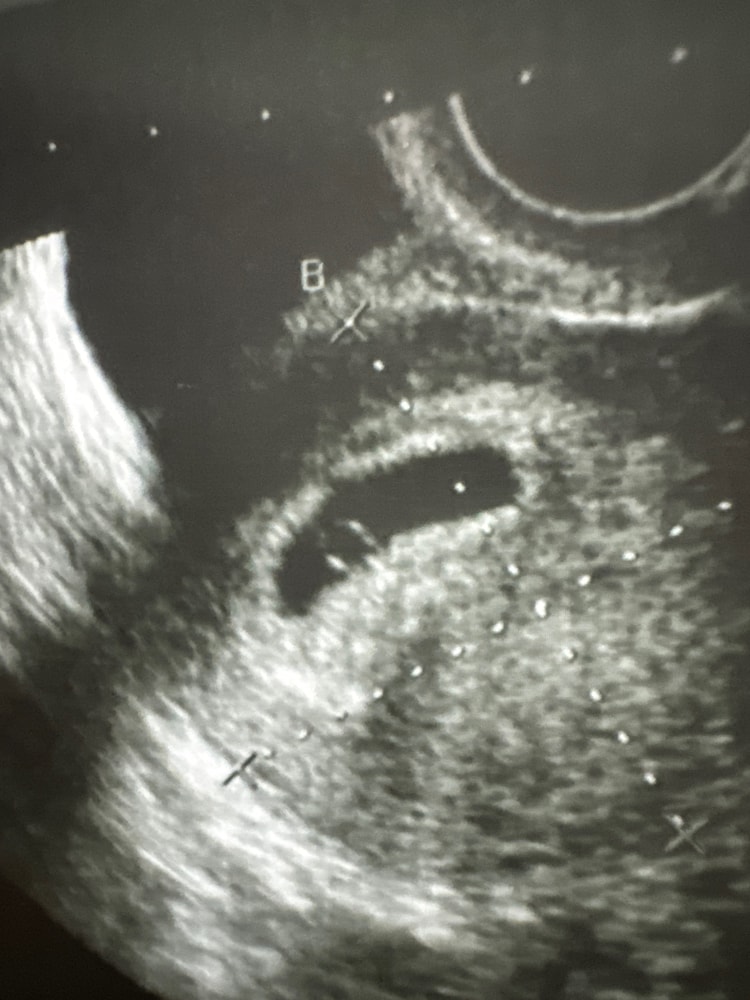

УЗИ, КТГ, доплерВчера сходила на узи, поставили срок 5 недель и 6 дней. Если я не ошиблась в том, что написал врач (очень непонятно написано), то размер ПЯ 21 мм, а КТР 4 мм.

Врач нашел эмбрион, я правда так и не поняла, где был эмбрион, а где желточный мешок, но мы смогли увидеть пульсацию, узит сказал, что это сердечко малыша. Но пока его нельзя измерить или услышать.

фасолинка)))

Черные дыры из которых потом вырастают дети , это мой младший сын сказал когда посмотрел на свое такое первое фото)))) Растите🙏